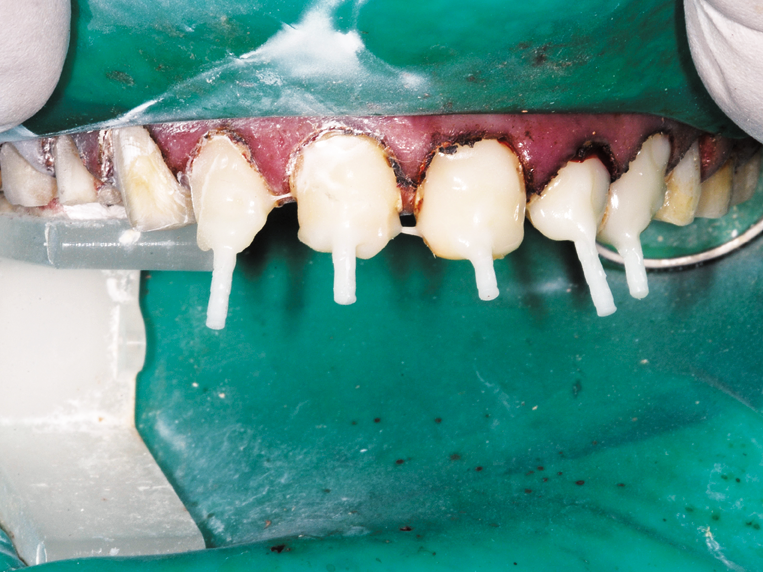

On the maxillary preparation day the entire upper arch was anesthetized with articaine with 1:100,000 epinephrine and a full arch rubber dam placed (Fig. 4). The severely damaged anterior teeth #7-11 were cleaned and shaped for gutta percha final fill, then prepared for the fiber core posts (Fig. 5). Bisco’s dual-cured UNIVERSAL PRIMER was placed and agitated for 30 seconds on all five teeth at once.

After thorough drying with air and paper points, the CORE-FLO DC LITE was injected into the canals one at a time with the fiber core posts immediately inserted. Each tooth was shaped and built up by adding CORE-FLO DC LITE as needed (Fig. 2, 6).